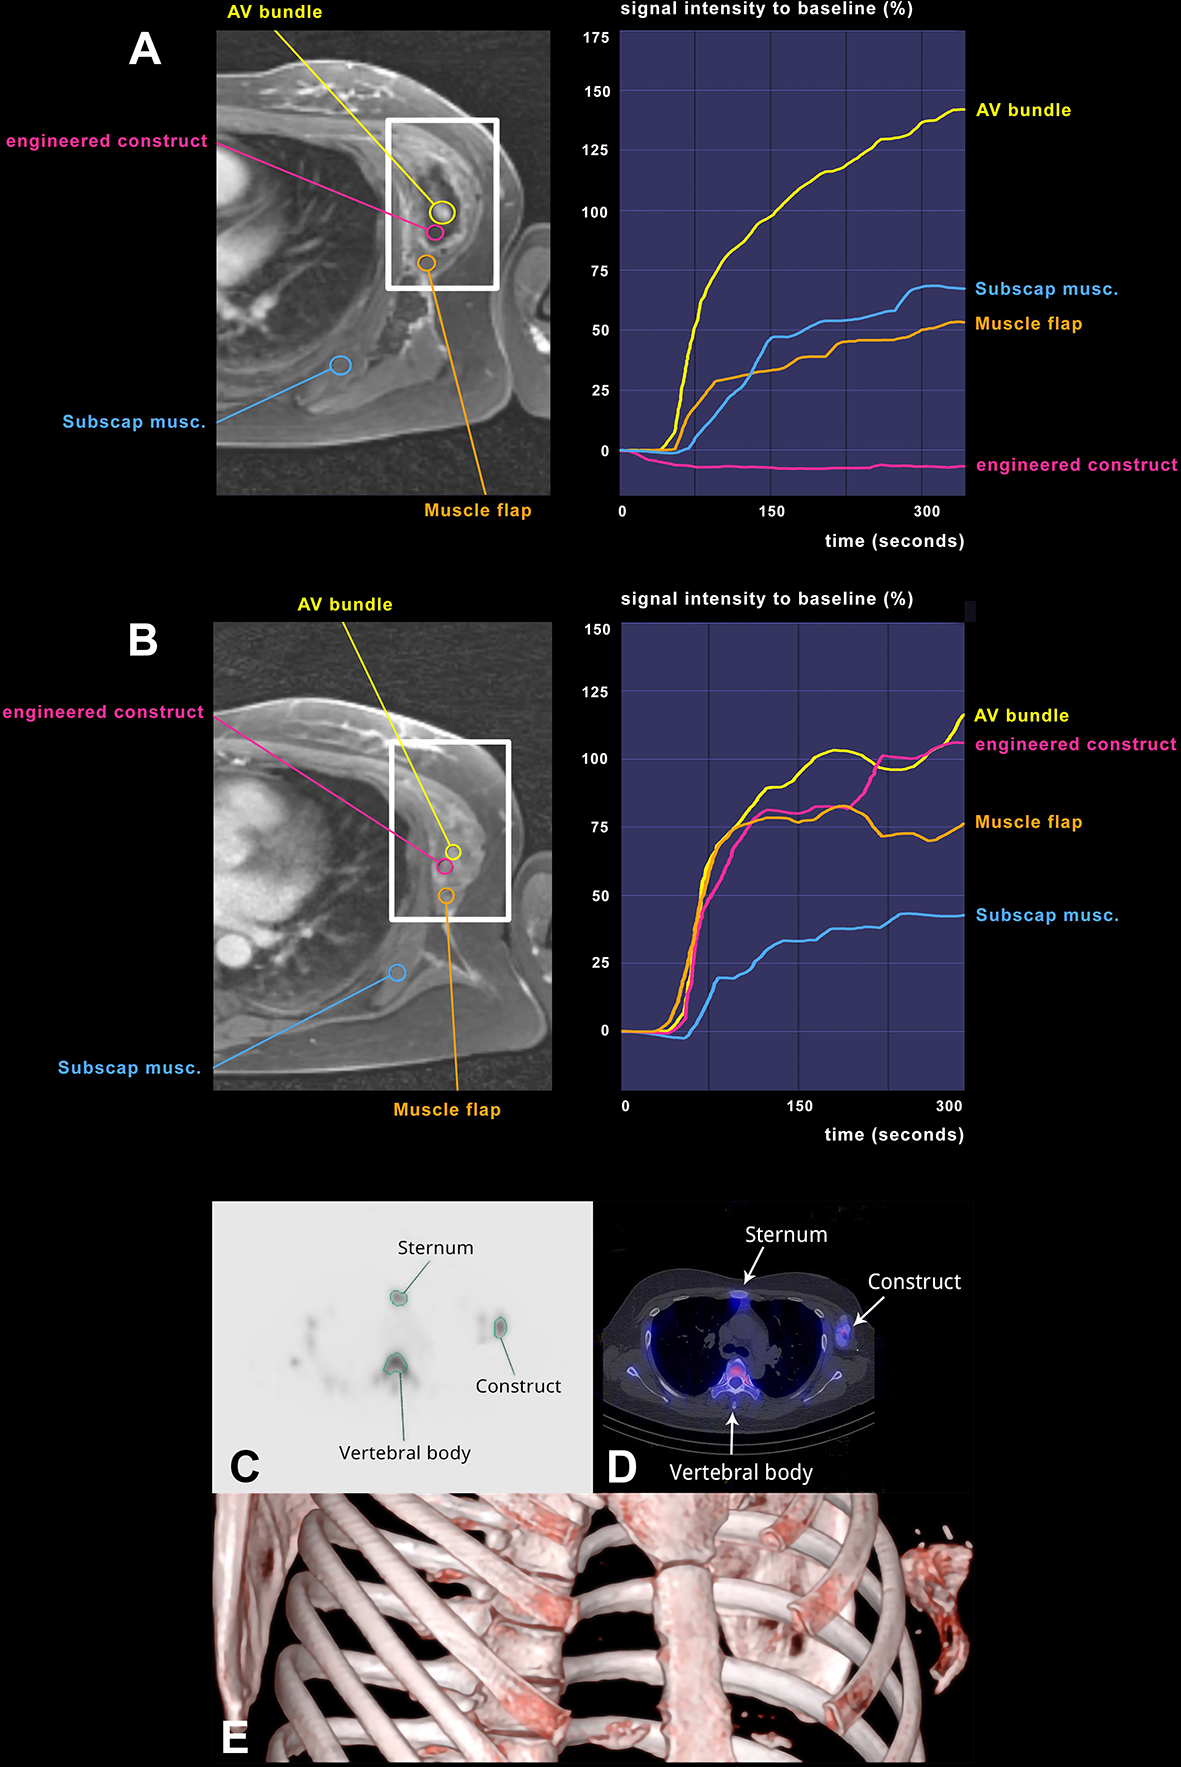

Vascularization of the construct was assessed during ectopic graft development after 1 week (Figure 3A) and 6 weeks (Figure 3B) by dynamic contrast-enhanced MR perfusion imaging. The AV bundle proved to be patent, providing intrinsic perfusion to the construct. The latissimus dorsi muscle wrap was viable, with a perfusion pattern comparable or superior to the subscapularis muscle, chosen as a reference for physiological perfusion in this anatomic region. At both time points, the subscapularis muscle, the latissimus muscle, and the AV bundle showed a normal, steadily increasing perfusion over time. When focusing on the engineered construct, no signal increase after injection of the contrast agent was observed after 1 week, whereas a steep increase in signal intensity was visible after 6 weeks, demonstrating functional internal vascularization.

Figure 3

Longitudinal assessment of vascularization and bone formation. Transversal images of a golden-angle radial sparse parallel (GRASP) MRI showing the perfusion of the engineered construct adjacent to the left ribcage over time as well as corresponding signal-time curves at 1 week (A) and at 6 weeks (B). The Maxilla construct is highlighted by white rectangles. Signal intensity in relation to t = 0 (injection of contrast agent) on the Y-axis, time in seconds on the X-axis. Violet region of interest (ROI) located in the construct, blue ROI located in the left M. subscapularis in situ and yellow ROI encompassing the AV bundle. Orange ROI indicates M. latissimus dorsi flap covering the construct. M. subscapularis was used as a reference for physiological vascularization in this area. Planar images (C) and SPECT and SPECT/CT images (D) after 6 weeks of the bone scintigraphy, showing strong DPD uptake in the construct, indicating bone turnover and vitality of the construct. In a region-of-interest (ROI) analysis of the maxilla construct at its largest diameter in comparison to the sternum (as a bone with similar structure/size). (E) VRT (volume rendering technique) from the SPECT illustrates the location of the prefabricated construct.

Bone metabolism of the construct was assessed after 6 weeks by SPECT/CT (Figures 3C–E). Active 3,3-diphosphono-1,2-propanodicarboxylic acid (DPD) uptake in the construct revealed traits of viable bone tissue (maximum counts: 112), in the range between the sternal bone (maximum counts: 95) and the highly compact thoracic vertebral body (maximum counts: 154), used as reference structures of similar size and position (Figures 3C, D). Bone biopsy at the phase of construct transfer, 32 weeks after ectopic implantation, morphologically confirmed de novo bone formation (Figures 2E–G). Masson Trichrome staining showed a clear distinction between the Tutoplast® scaffold material, consisting of devitalized bone, and newly deposited bone matrix. The latter was less dense and less mature, as shown by the green color and reduced lamellar structure. The deposited bone contained stained cell nuclei as sign of living tissue, clearly distinguishable from the devitalized bone of the scaffold, where cells were visible as empty lacunae. Vascularization of the construct was histologically verified by piercing vessels in the scaffold material (Figures 2F, G). Osteoclasts were found around the Tutoplast® scaffold, which displayed morphological signs of active resorption. Within the newly formed, apposed bone, there was no major osteoclast infiltration and no signs of degradation. Quantitative histomorphometry of the biopsy specimen indicated an average of 30.2% (SD = 10.3) of newly formed bone over the total bone area.